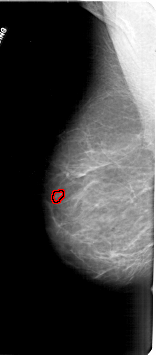

A_1711_1.LEFT_MLO

LEFT_MLO LINES 6736 PIXELS_PER_LINE 2956 BITS_PER_PIXEL 12 RESOLUTION 43.5 OVERLAY

FILE: A_1711_1.LEFT_MLO.OVERLAY

TOTAL_ABNORMALITIES 1

ABNORMALITY 1

LESION_TYPE MASS SHAPE LOBULATED MARGINS CIRCUMSCRIBED

ASSESSMENT 4

SUBTLETY 3

PATHOLOGY BENIGN

TOTAL_OUTLINES 1

BOUNDARY